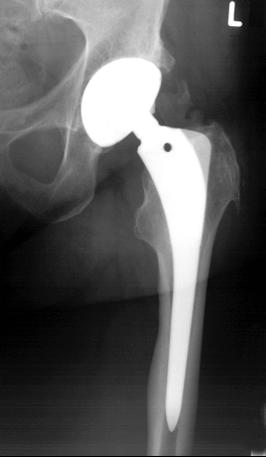

Der Prothesenschaft verankert die Hüftprothese im Oberschenkelknochen (Femur). Im Beckenbereich übernimmt die im Beckenknochen verankerte Gelenkpfanne die Fixierung der Prothese. Die computerunterstützte Planung anhand standardisierter Röntgenbilder gewährleistet, dass der Hüftspezialist die Bewegungsgeometrie im Hüftgelenk sowie die Beinlänge des Patienten erhält. So können wir für unsere Patienten ein natürliches Tragegefühl der Hüftprothese erreichen und Luxationen (Ausrenken des Hüftkopfes) vorbeugen.

Der Schaft der Hüftprothese wird in den inneren Markraum des Oberschenkelknochens eingebracht. Am Prothesenschaft befindet sich oben ein freistehender Steckkonus. Dieser verbleibt außerhalb des Oberschenkelknochens. Auf ihn wird später der kugelförmige Prothesenkopf aufgesetzt. Der Prothesenschaft verankert die Hüftprothese möglichst lockerungsfrei im Oberschenkel.

Der Prothesenschaft soll die Hüftprothese möglichst lockerungsfrei im Oberschenkel verankern.

Eine sehr belastbare Form der Befestigung im Knochen ist die einwachsende Hüftprothese: Der Schaft hat eine raue Titanoberfläche, die die Verbindungsfläche vergrößert und so die Verbindung zwischen Knochen und Metall zusätzlich stabilisiert. Auf diese Weise kann das Knochengewebe des Oberschenkels dauerhaft einwachsen.

Bei der Operation wird die einwachsende Hüftprothese zunächst stabil in das Innere des ausgehöhlten Röhrenknochens eingebracht und verkeilt. Sechs Wochen nach der Operation ist die knöcherne Integration des Prothesenschaftes durch einwachsendes Knochengewebe weitgehend abgeschlossen.